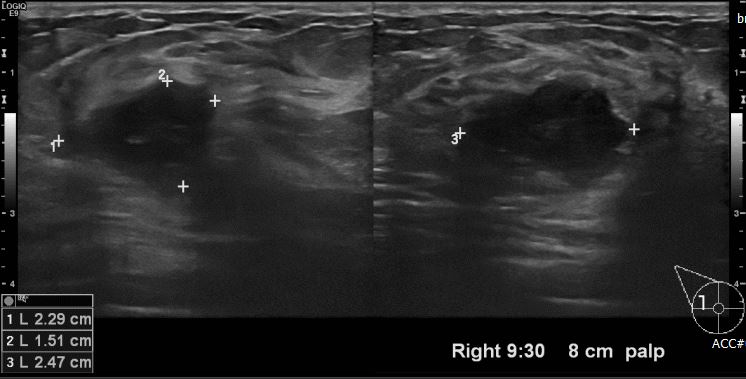

유측 유방에 만져지는 멍울로 내원하신 30대 여성분으로 본원 유방초음파상

우측 9시30분 방향에서 8cm 떨어진 거리에 만져지는 멍울 조직검사 시행하여

우측 침윤성 유관암 진단 되었습니다.